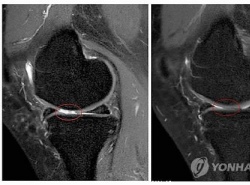

"ÀÚ°¡Áö¹æ¼¼Æ÷ À̽Ä, ÅðÇ༺°üÀý¿°¿¡ È¿°ú" (¼¿ï=¿¬ÇÕ´º½º) ÇѼº°£ ±âÀÚ = ÀÚ½ÅÀÇ Áö¹æÁ¶Á÷¿¡¼ äÃëÇÑ ÀÚ°¡Áö¹æ¼¼Æ÷ À̽ÄÀÌ ÅðÇ༺ °üÀý¿° Ä¡·á¿¡ È¿°ú°¡ ÀÖ´Ù´Â ¿¬±¸°á°ú°¡ ³ª¿Ô´Ù. ¼¼Æ÷Ä¡·á¡¤¸é¿ª¿ä¹ý ...